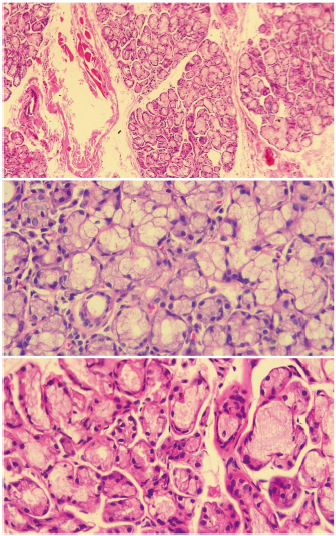

Of the total of patients with dry symptoms, FLS was found in 8 (8.7%) of them (see Figs. 1 and 2), according to the FS (the focus score was found between l and 2 in 7 of the patients and only in one was higher than 2, while 38 (41.30%) had a positive biopsy by CM (grades 3 and 4). All patients who were positive by the CM method, but who were negative for SS when the FS classification was used, had chronic non-specific sialadenitis by said method, except one who presented chronic sclerosing sialadenitis. According to the ACR/EULAR criteria scores (2016), the frequency of SS was determined in 24 (26.09%) patients when the FS method was used for MSGB (this frequency included the 8 with positivity for FLS according to FS) and in 32 (34.78%) patients when the CM method was used; all cases were recorded in women. The remaining 6 patients with positivity by CM were classified as patients with dry syndrome, who, although they were positive through this reading in the MSGB, were not positive in the other criteria for SS. With respect to age, the highest frequency of SS was between 41 and 65 years for both histopathological methods (FS: 83.3%; CM: 78.3%).

Fig. 1 Histology of normal minor salivary gland. A salivary gland with normal histology of a patient included in the study is observed in the three slices, in which mucinous acini with myoepithelial cells and ductus are seen. The upper image at 10× magnification and the lower images at 40× magnification. Source: own elaboration.

Fig. 2 Histology of an altered minor salivary gland. The upper left image shows a salivary gland biopsy of a patient included in the study, in a 10× slice with an aggregate of lymphoid cells (yellow arrow) adjacent to a normal-appearing salivary gland (blue circle). In the upper right image, the same aggregate is observed at a magnification of 40×. This aggregate can be counted as a focus. In the lower left image, a dense aggregate of lymphocytes is observed in the salivary gland background of one of the patients analyzed in the study, with atrophy and ductal dilation. In the lower image on the right, we can see a salivary gland biopsy with ductal ectasia (arrow) and atrophy. Source: own elaboration.